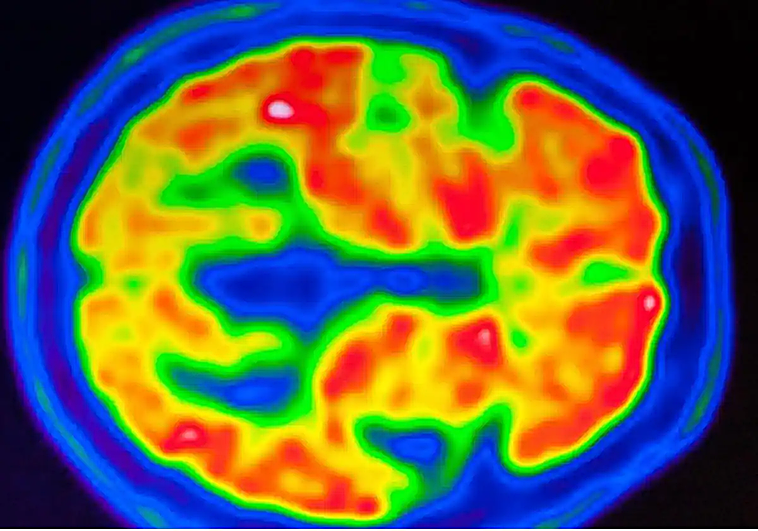

En una serie de experimentos, se evaluó la percepción y la memoria de los participantes mientras registraban su actividad cerebral utilizando un escáner de imágenes por resonancia magnética funcional (fMRI). El equipo identificó un mecanismo de codificación push-pull, que gestiona la interacción entre las áreas de percepción y memoria en el cerebro.

Los resultados muestran que cuando se ilumina la retina, Las áreas visuales del cerebro responden aumentando su actividad para representar el patrón de luz.. Las áreas de memoria del cerebro también responden a la estimulación visual, pero a diferencia de las áreas visuales, la actividad neuronal disminuye cuando realizas el mismo comportamiento visual.